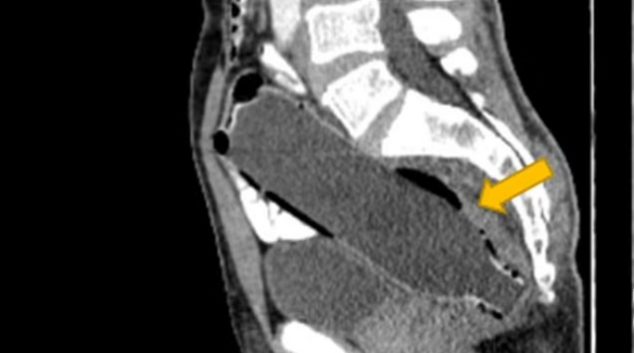

8-годишно момче не престанало да кашла цели 5 години! Причината сите ги шокирала!

Марли Ењаковиќ (8) од Аделаида, почнал да кашла пред 5 години. Со тоа што постојано му давале нова дијагноза затоа што ништо не успевало. Мајката на Марли, Скај, рече дека нејзиниот син почнал да има напади на кашлање додека јадел, но како што одминувало времето тој кашлал со часови и тоа било едноставно страшно. Стигнале …